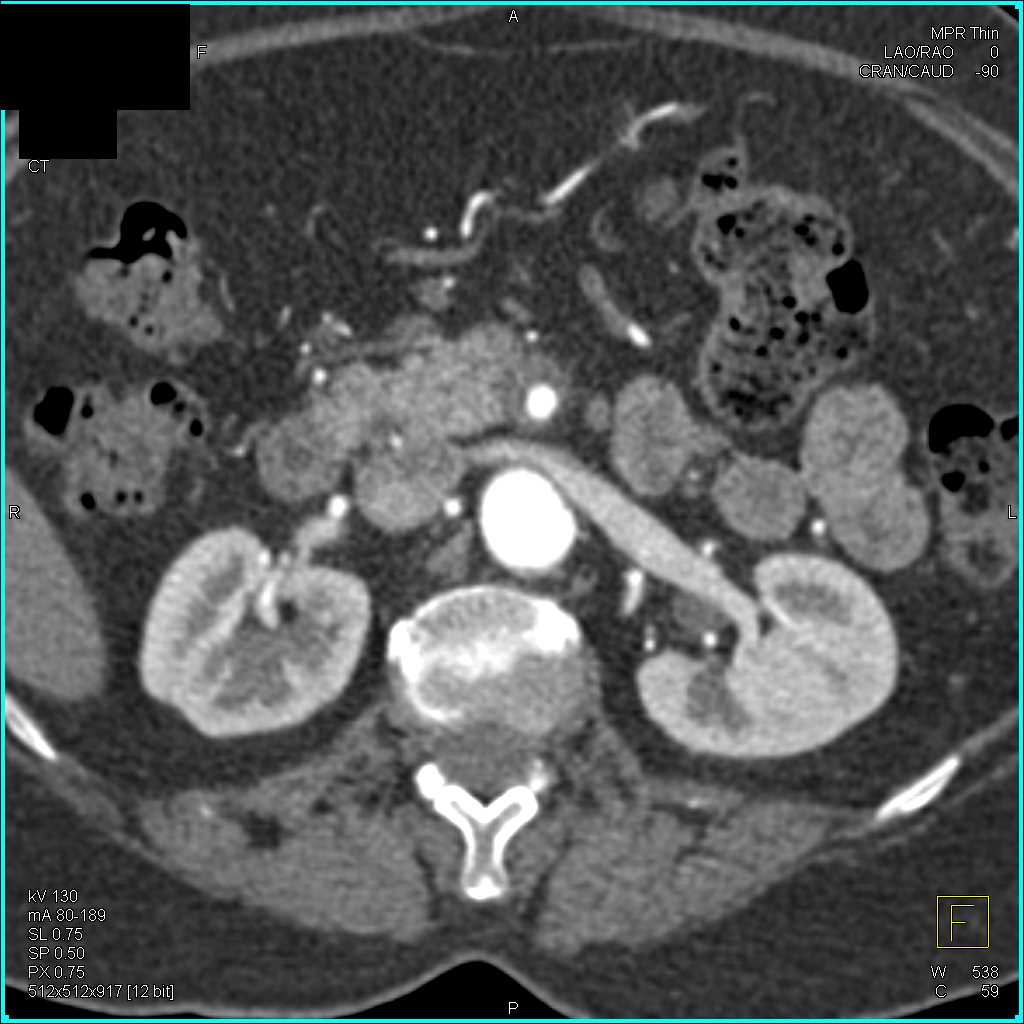

Neuroendocrine Tumor Body of Pancreas